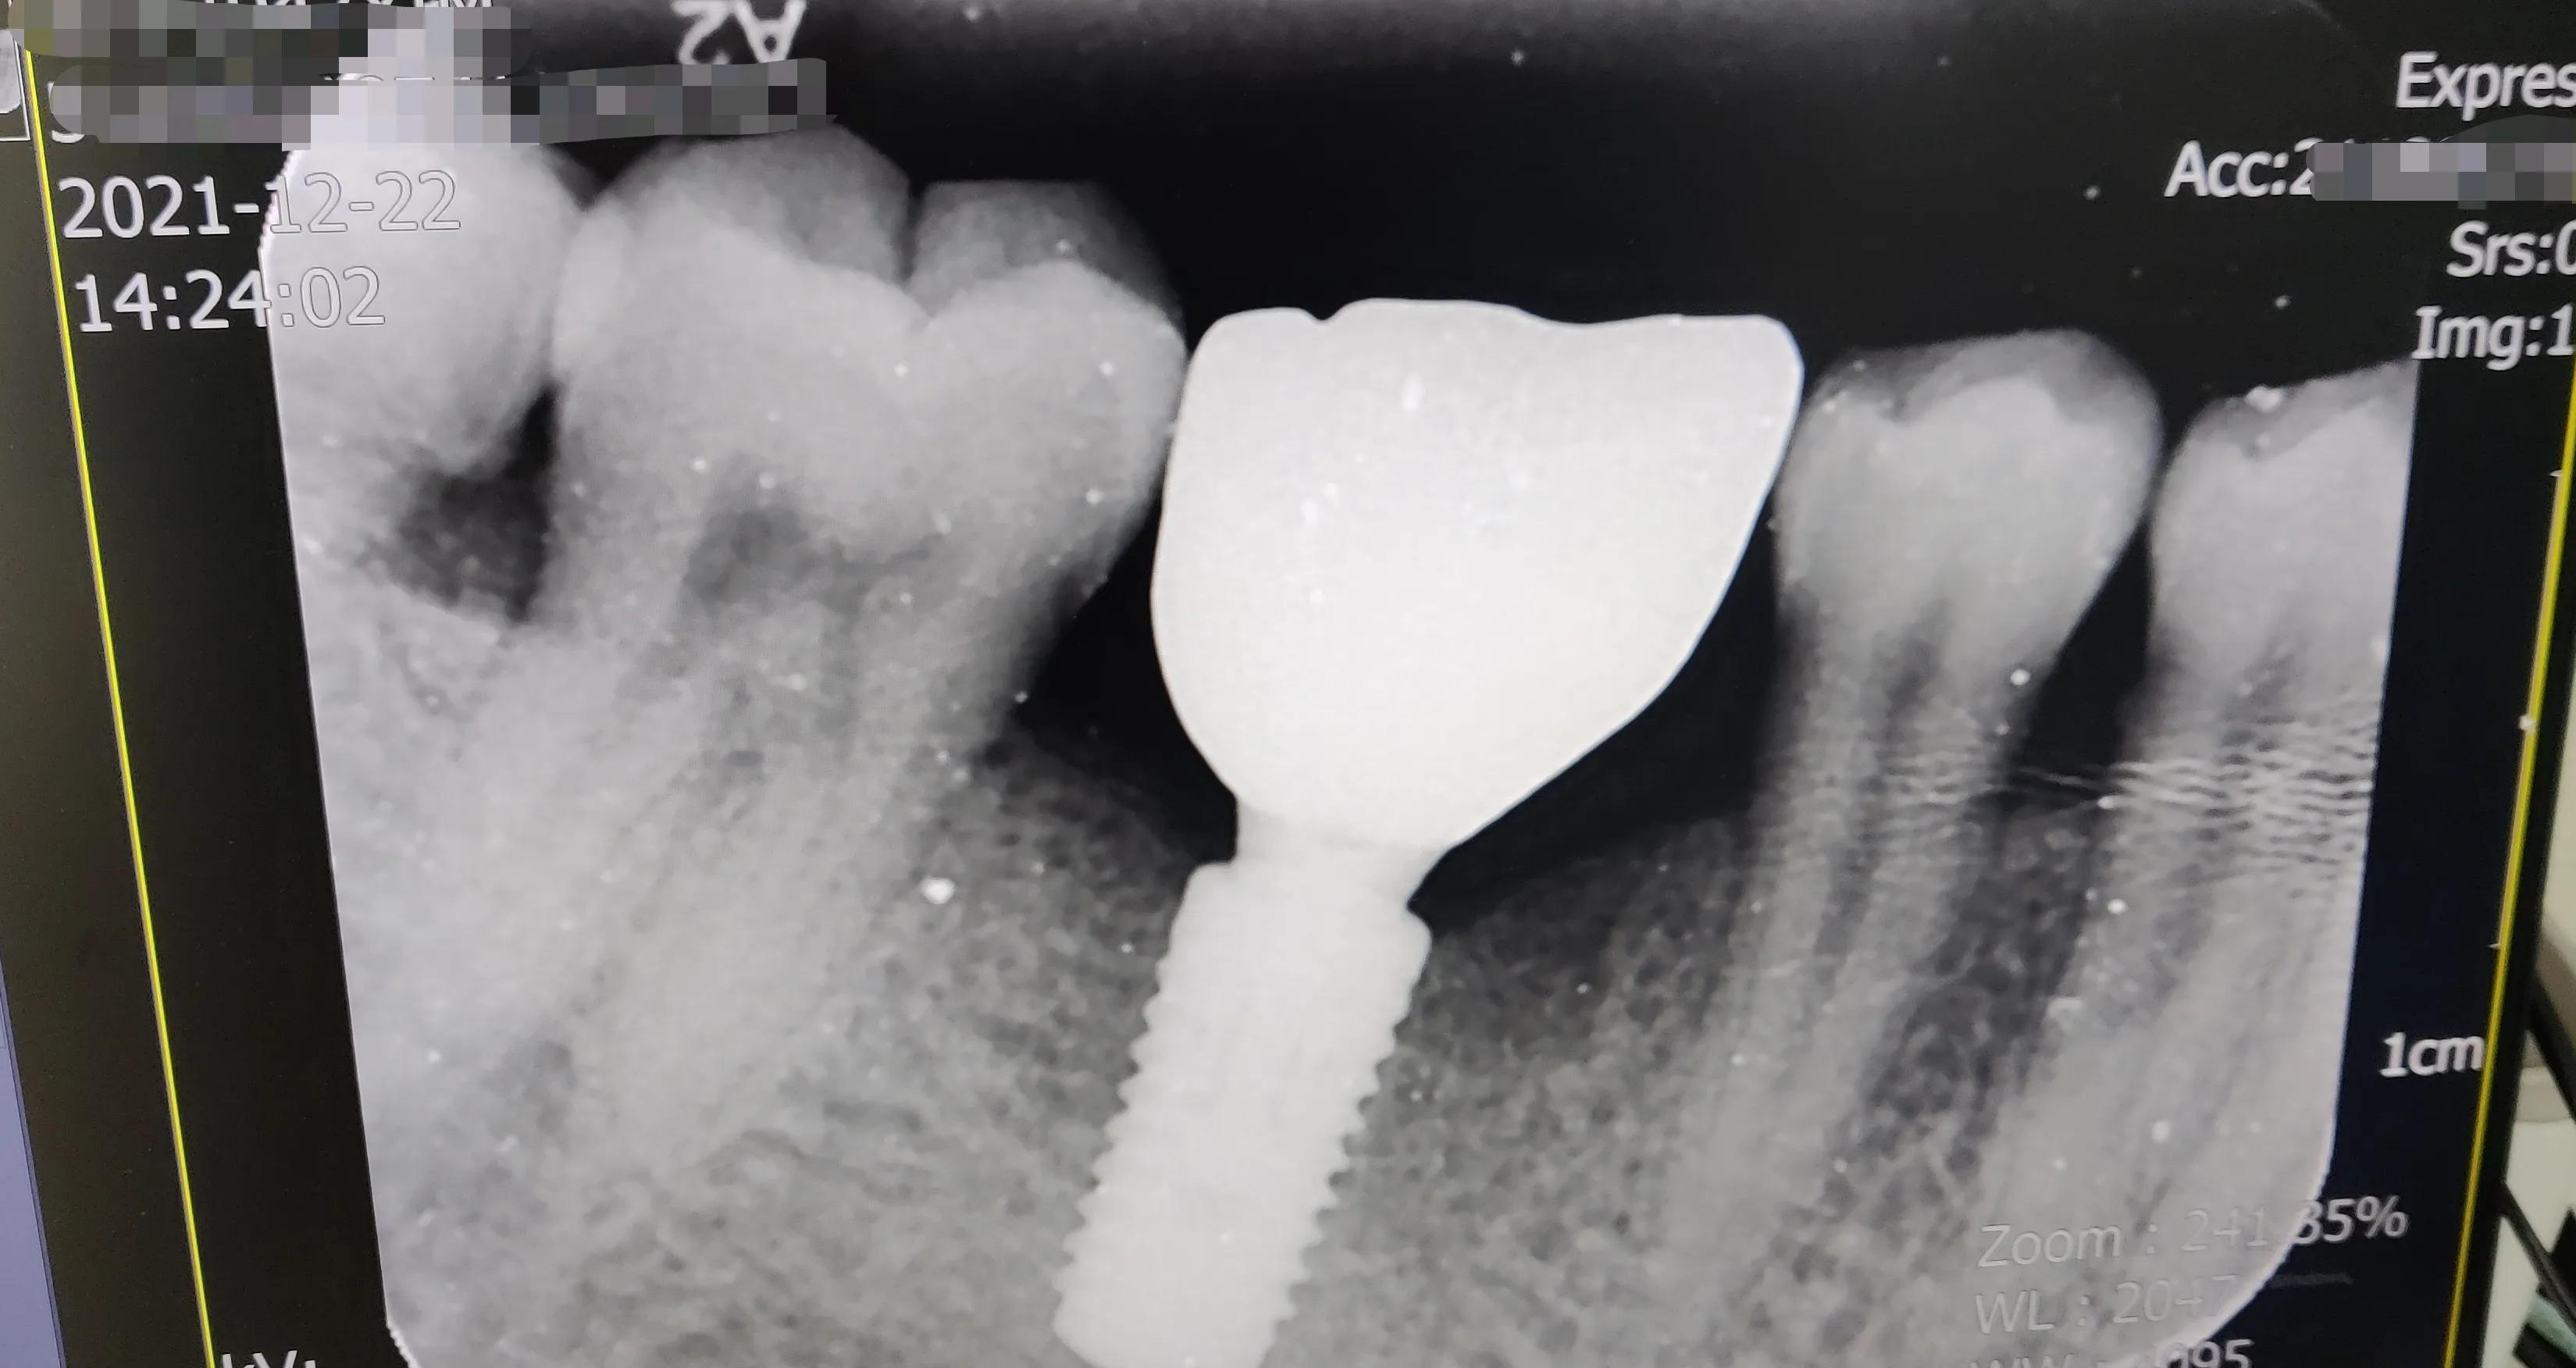

后,醫(yī)生會讓你再去拍個片,檢查一下終安裝果!

安裝好的片子

真假牙齒在X光片下“原形畢露”哈哈??!